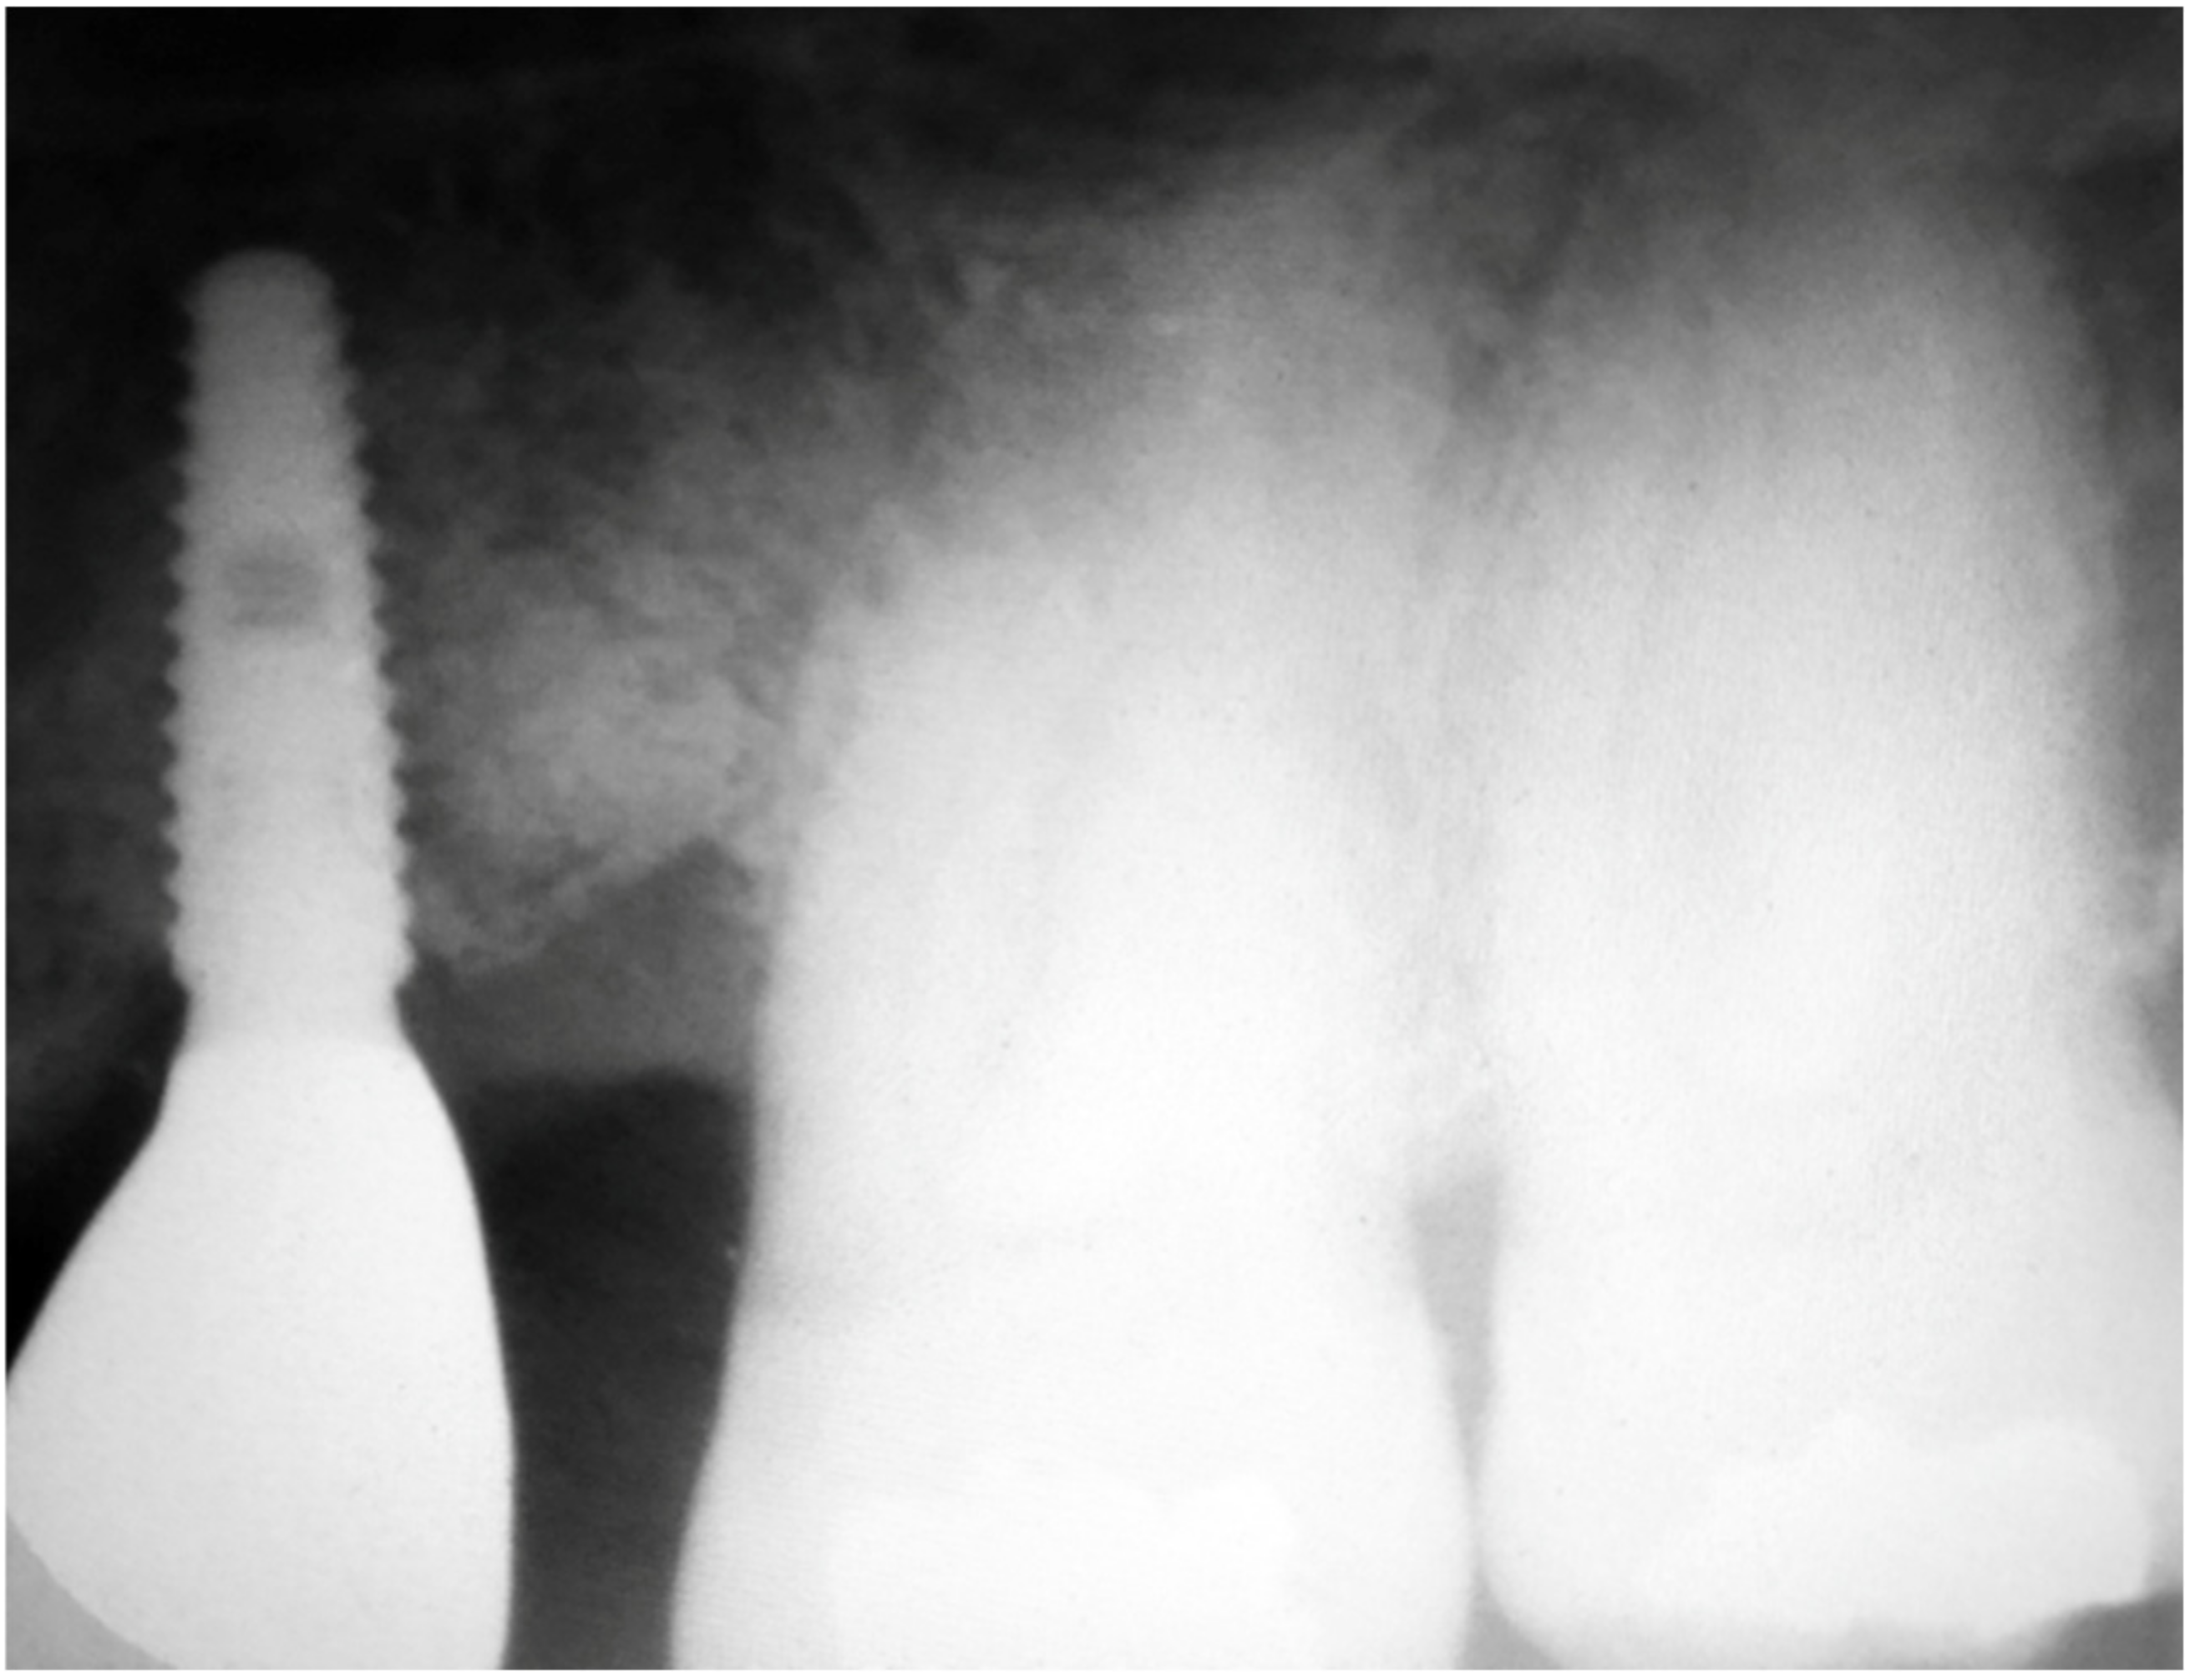

Figure 4.

Rx taken at a 5 year follow-up showing the stability of the regeneration on both implant and tooth side.

Three months after implant surgery the fixture was restored with a ceramic crown and a radiograph taken 5 years after augmentation. Figure 4 not only shows the perfect maintenance of the osseointegration after loading, but also how the GTR effect is visible on the mesial of tooth 26 with an attachment gain of 6 mm; the probing (PPD) at the time of recall was 3 mm The tooth remained in function and the patient can clean the area well with interproximal tooth brushes and dental floss.